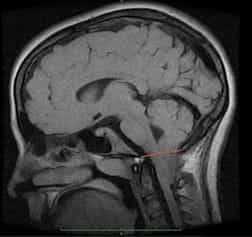

Рисунок 2.- МРТ пациента в 8 и 20 месяцев, на втором снимке можно наблюдать опущение миндалин мозжечка, которое появилось уже после первого МРТ. Huang P. “Adquired” Chiari I malformation. J. Neurosurg 1994. Это указывает на то, что, помимо наследственного и генетического фактора, существует фактор приобретенного заболевания.